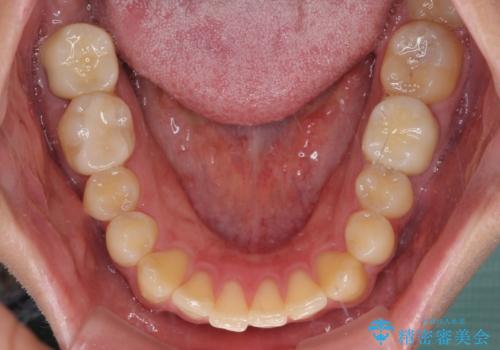

途中来院されない時期があったため、初診から終了まで期間がかかりましたが、根管治療を行った歯の根尖病変はいずれも改善を確認することができました。

口腔内の金属が全てなくなり、患者様には大変満足していただきました。